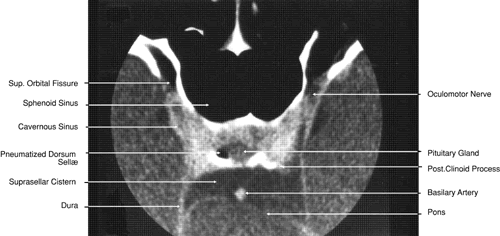

Fig. 27. Coronal images through cavernous sinus and optic chiasm. A. T1-weighted magnetic resonance imaging through anterior chiasm. B. Computed tomography image through anterior chiasm. C. Computed tomography image through posterior chiasm. D. Computed tomography image through optic tract.

Fig. 28. Axial computed tomography image with contrast medium through cavernous sinus and pituitary gland.